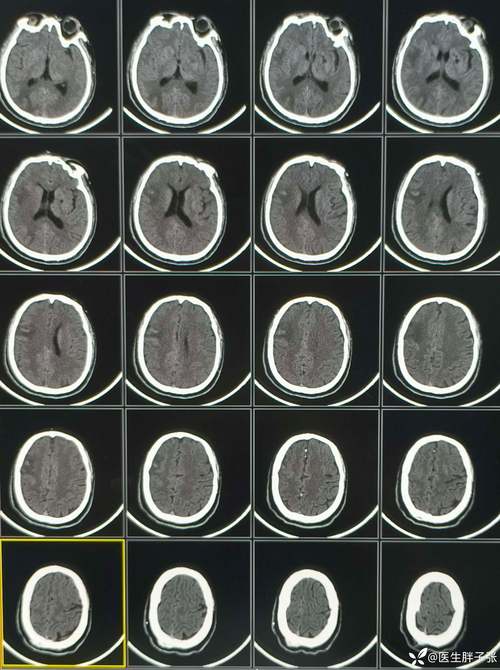

- 梗死灶形成:右侧大脑的某条动脉被堵死了,导致一大片脑组织缺血坏死(这就是梗死灶)。

- 脑水肿:坏死的脑组织会像一块泡水的海绵一样,迅速肿胀起来,这种肿胀会占据大量的空间。

- 空间被占,压力剧增:我们的颅骨是一个坚硬、封闭的“盒子”,容积是固定的,梗死灶和周围严重水肿的脑组织,就像在盒子里塞进了一个不断膨胀的气球,导致整个右侧大脑的压力急剧升高。

- 大面积脑梗死:通常只有梗死范围非常大,才会引起如此严重的脑水肿和颅内压增高。